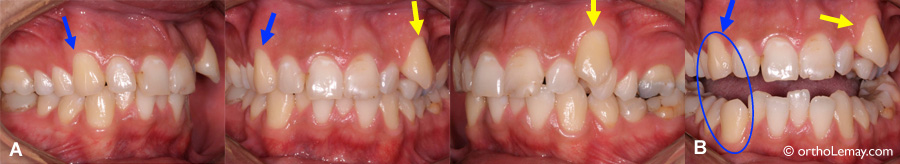

Ce jeune homme de 24 ans présente une situation où l’on peut comparer le rôle fonctionnel de la canine des deux côtés opposés. (A) La canine supérieure droite (flèche bleue) touche à la canine opposée et est fonctionnelle pendant les mouvements mandibulaires vers la droite. Elle commence déjà à montrer des signes d’usure; la pointe est rendue droite. Du côté opposé, la canine qui manque d’espace est hors de l’arcade (flèche jaune) et, par conséquent, elle n’est pas fonctionnelle, n’a aucun signe d’usure et le bout est encore très pointu tout comme au moment où cette dent est sortie. (B) Lorsque la bouche est ouverte, on peut mieux apprécier la différence entre la pointe des deux canines et constater que les canines de droite présentent déjà une usure significative pour un jeune adulte (cercle). Les canines de gauche étant moins fonctionnelles, ce sont les incisives qui doivent donc guider la mâchoire pour certains mouvements et ceci contribue à l’usure de leurs bords incisifs. (Homme – 24 ans)